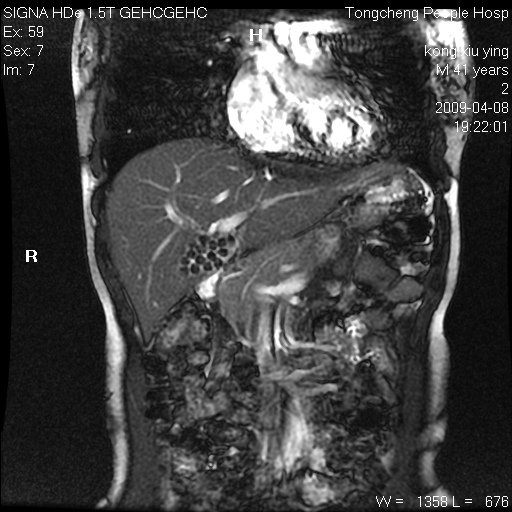

标题: CL1008:【经典】胆囊石榴籽样结石。

女,41岁。健康体检——彩超提示:胆囊显示不清。平素健康,无不适感。

腹部mr扫描及mrcp,图像如下: